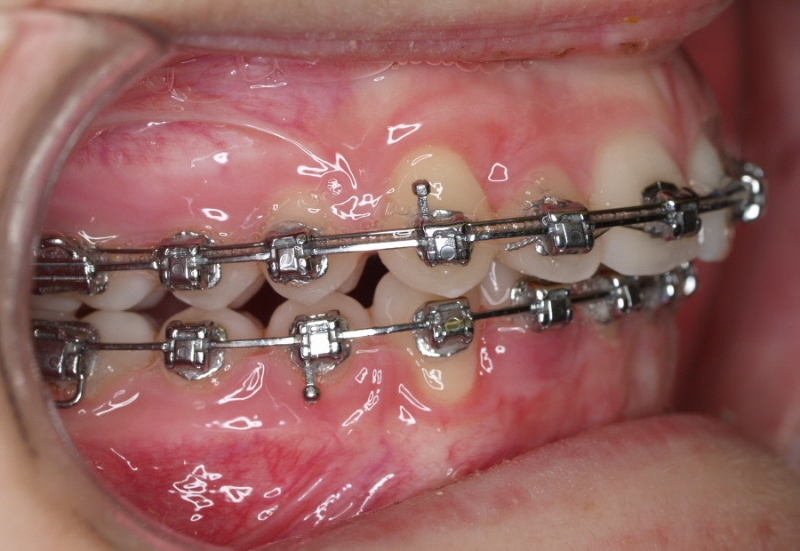

Clase II paciente 15 años

Con lo que decide realizarse un tratamiento de ortodoncia de duración de 24 meses con brackets damon Q.

CASO COMPLETO: